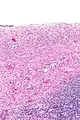

Ovarian serous cystadenoma. The cystic space is at the top of the image. Ovarian parenchyma is seen at the bottom right. H&E stain.

Serous cystadenomas are diagnosed by histomorphologic examination, by pathologists. Grossly, they are, usually, small unilocular cysts that contain clear, straw-coloured fluid. However, they may sometimes be multilocular. Microscopically, the cyst lining consists of a simple epithelium, whose cells may be either:[3]

• be columnar and tall and contain cilia, resembling normal tubal epithelium

• be cuboidal and have no cilia, resembling ovarian surface epithelium